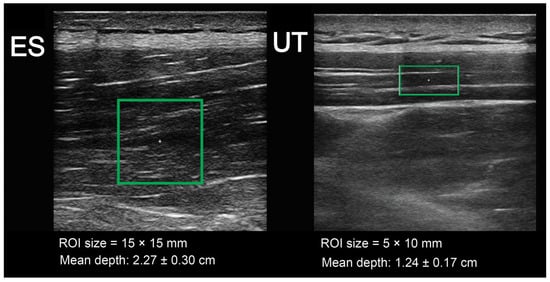

2.4. Muscle Stiffness Assessment